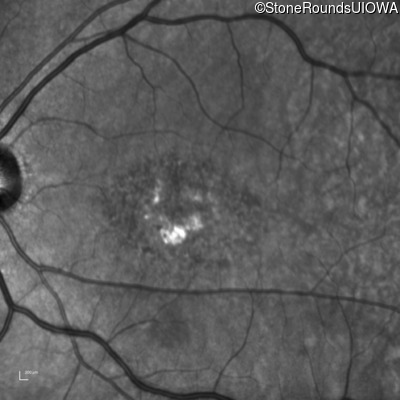

Infrared Fundus Photograph - Right - 20/200 +2

Exemplar